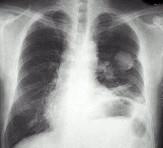

问题 男,67岁,胸痛半月,胸片检查如图,最可能的诊断为()

选项 A.左上肺结核球 B.左上肺周围型肺癌 C.左上肺炎性假瘤 D.左上肺球形不张 E.左上肺脓肿

答案 B